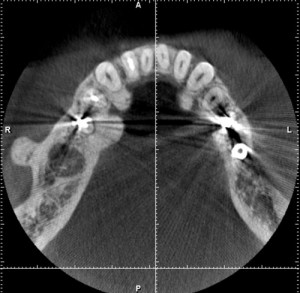

虫歯で抜歯になり、抜歯後6カ月のCT画像。なんだか、穴が開いたままで、ちっとも骨で埋まっていないように、見えた(緑→)。うっすらと、骨の蓋ができているようにも見える(黄→)が、当院の伊藤医師とも相談し、外側に突き出ている骨の出っ張り(ピンク→)をとって、穴を埋める事を念頭に入れて手術を開始した。

結果は、骨の蓋ができており、通常通りインプラントが入れられた。骨の出っ張りは、患者さんは元々気にされていなかったので、そのままにした。骨が出っ張る原因は歯ぎしりが考えられている。インプラントに被せ物が入った後は、歯ぎしり防止用のマウスピースがあったほうがいい。青→は私が17年前に入れた初期のタイプのインプラント。まだ、もっている。(長谷川)

下顎輪切りCT画像 R(患者さんにとっての右)L(患者さんにとっての左)緑→(骨密度の低い部分、一見穴になっているように見える)黄→(穴をふさぐようにできている骨のふた)ピンク→(骨のでっぱり)青→(インプラント)